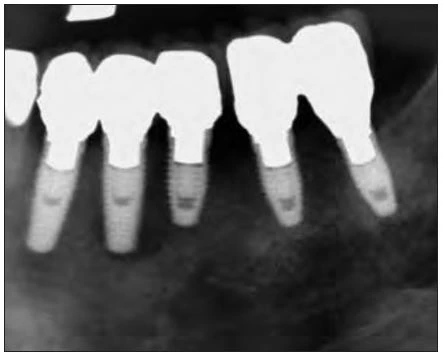

Hình 6: X quang cho thấy vùng tiêu xương đáng kể quanh implants ở phía sau góc phần tư bên trái của xương hàm dưới.

Vào tháng chín 2006, một phụ nữ 81 tuổi được cấy tổng cộng chín implants, năm trong số chúng được thể hiện trong hình 6: vị trí răng nanh trái hàm dưới, răng cối nhỏ thứ nhất và thứ hai, răng cối lớn thứ nhất và thứ hai. Sau 4 tháng, phục hình tạm được thực hiện, và sau 6 tháng bệnh nhân được mang phục hình chính thức. Sau 1 năm, bệnh nhân than phiền về tình trạng sưng tấy quanh implant. Kiểm tra X quang cho thấy tình trạng tiêu xương đáng kể quanh implants ở vùng phần tư phía sau hàm dưới bên trái (Hình 6). Khi cấu trúc trên cùng bị loại bỏ, người ta phát hiên ra rằng implants không hề bị lỏng. Tuy nhiên, tình trạng viêm đã lan sang viêm-đây là một trường hợp rõ ràng của viêm quanh implant tiến triển. Những kiểm tra khác xác định rằng đây là một ca CIST (liệu pháp hỗ trợ ngăn chặn tích tụ – cumulative interceptive supportive therapy) loại D ( độ sâu túi > 5mm, có chảy máu khi thăm khám, và tiêu xương > 2mm). Sau khi tiêm thuốc tê tại chỗ (2% xylocaine), vạt phía má được lật lên ở vị trí phần tư hàm dưới trái. Tuy implants không bị lỏng, nhưng lại thấy tình trạng tiêu xương đáng kể và sự hình thành mô hạt (Hình 7). Mô hạt nhiễm khuẩn được cắt bỏ và lấy đi bằng tia laser với đầu PS600T ở năng lượng 50mJ và 20 PPS kèm với phun nước tiệt trùng ở lưu lượng 5mL/min (Hình 8a và 8b). Mô hạt thường được loại bỏ bằng nạo, nhưng máu chảy ra do nạo làm vùng điều trị không được nhìn rõ ràng. Sử dụng tia laser Er:YAG cùng phun nước để loại bỏ vấn đề này. Việc áp dụng phun nước và những sự nổ vi thể (xảy ra khi tia laser bắn vào nước) sẽ giúp giữ cho vùng làm việc luôn được nhìn thấy rõ ràng.